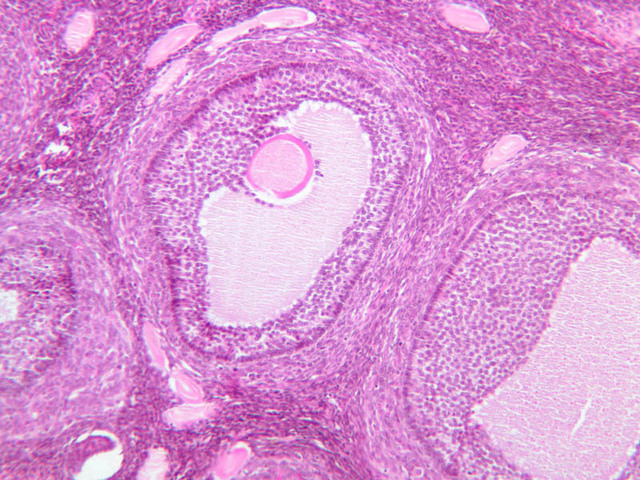

The ovary is a somewhat oval and slightly flattened organ situated near the fimbriated end of the uterine tube (B-94, monkey ovary, H&E [1x, 1x]; B-95, monkey ovary, H&E [1x-labeled, 1x]; B-96, monkey ovary and tube, H&E [1x]; B-54, H&E [1x, 1x]). Its exposed surface is covered by a mesothelial sheet of squamous or cuboidal epithelium. Just deep to this is an ill defined area of dense fibrous connective tissue referred to as the tunica albuginea (B-96 [2.5x-labeled, 10x-labeled, 20x, 40x]).

The ovary has two major regions – the cortex and the medulla. The cortex is the broad peripheral area containing follicles in various stages of development, whereas the medulla is the more central area displaying profiles of large blood vessels. These blood vessels gain entrance via the mesovarium. The division between the cortex and medulla is indistinct. In the cortex, stromal cells occupy the areas between the follicles. These cells are closely packed, fusiform (spindle shaped), and have the potential to differentiate into a specialized component of the maturing follicle (theca folliculi).

Mature (Graafian) Follicle

At maximum size, follicles will bulge from the ovarian surface and occupy the full thickness of the cortex. The oocyte is displaced to one side of the antrum where it is surrounded by a thickening of granulosa cells. This stalk-like thickening is referred to as the cumulus oophorus. A distinct basal lamina separates the granulosa cells from the theca. The theca has segregated itself into the theca interna and the theca externa. The theca interna is adjacent to the basal lamina, highly vascular and consists of secretory cells. The theca externa is connective tissue that merges with the adjacent stroma. Mature (Graafian) Follicle (slide B-94 [2.5x, 10x, 20x-labeled] [10x, 20x, 40x] [10x, 20x, 40x])